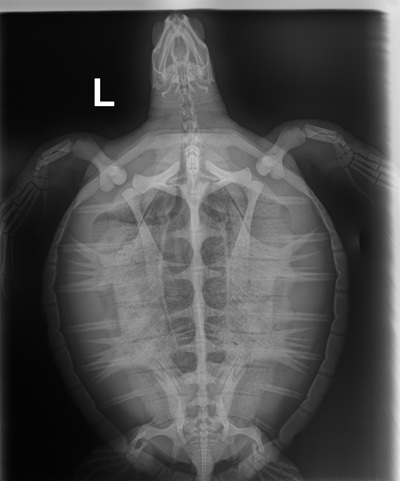

8.9 lbs non-FP juvenile green

Fishing line wrapped around Left Front Flipper and into mouth (no internal hook). Small hook wound to left shoulder. Small notch out of left marginal scutes but already healing.